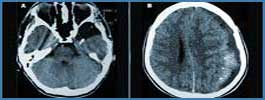

Tomografie computerizată cranio-cerebrală

Prin computer tomografie se poate studia anatomia părţilor moi faciale şi de la nivelul neurocraniului.

Evidenţierea sistemului osos atât la nivelul feţei cât şi la nivelul bolţii şi bazei craniului sunt de domeniul computer tomografiei.

Se recomandă examinare CT în situaţiile în care clinicianul suspicionează o afecţiune a sistemului nervos de origine malformativă, vasculară (infarcte cerebrale şi hemoragii intra-craniene, malformaţii ale vaselor), tumorală sau degenerativă.